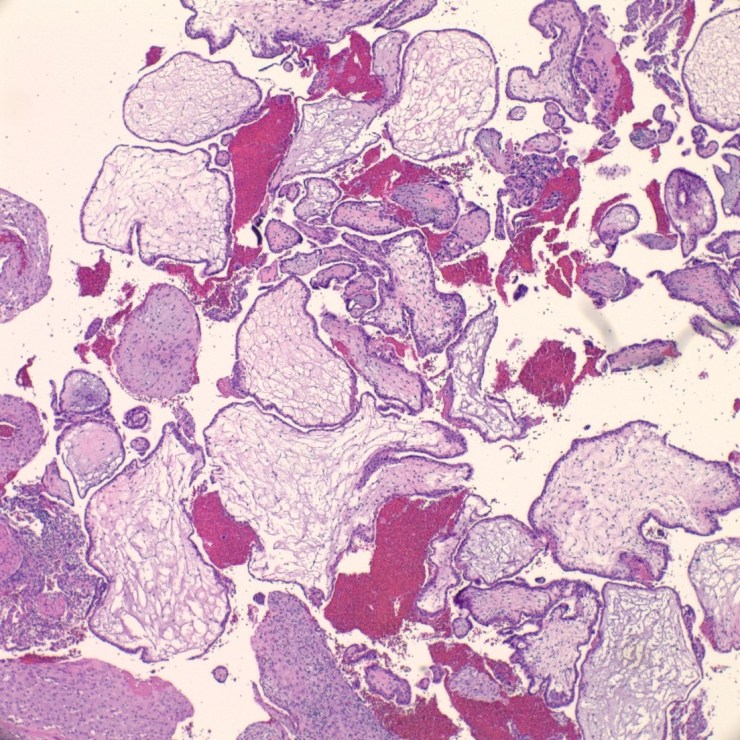

COMPLETE HYDATIDIFORM MOLES:

- Grossly large amount of tissue (5 cm and more) with sometimes large ballooned villi (>1 cm).

- Presence of cisterns, circumferential or almost circumferential trophoblastic proliferation and trophoblastic inclusions (figure 3-4).